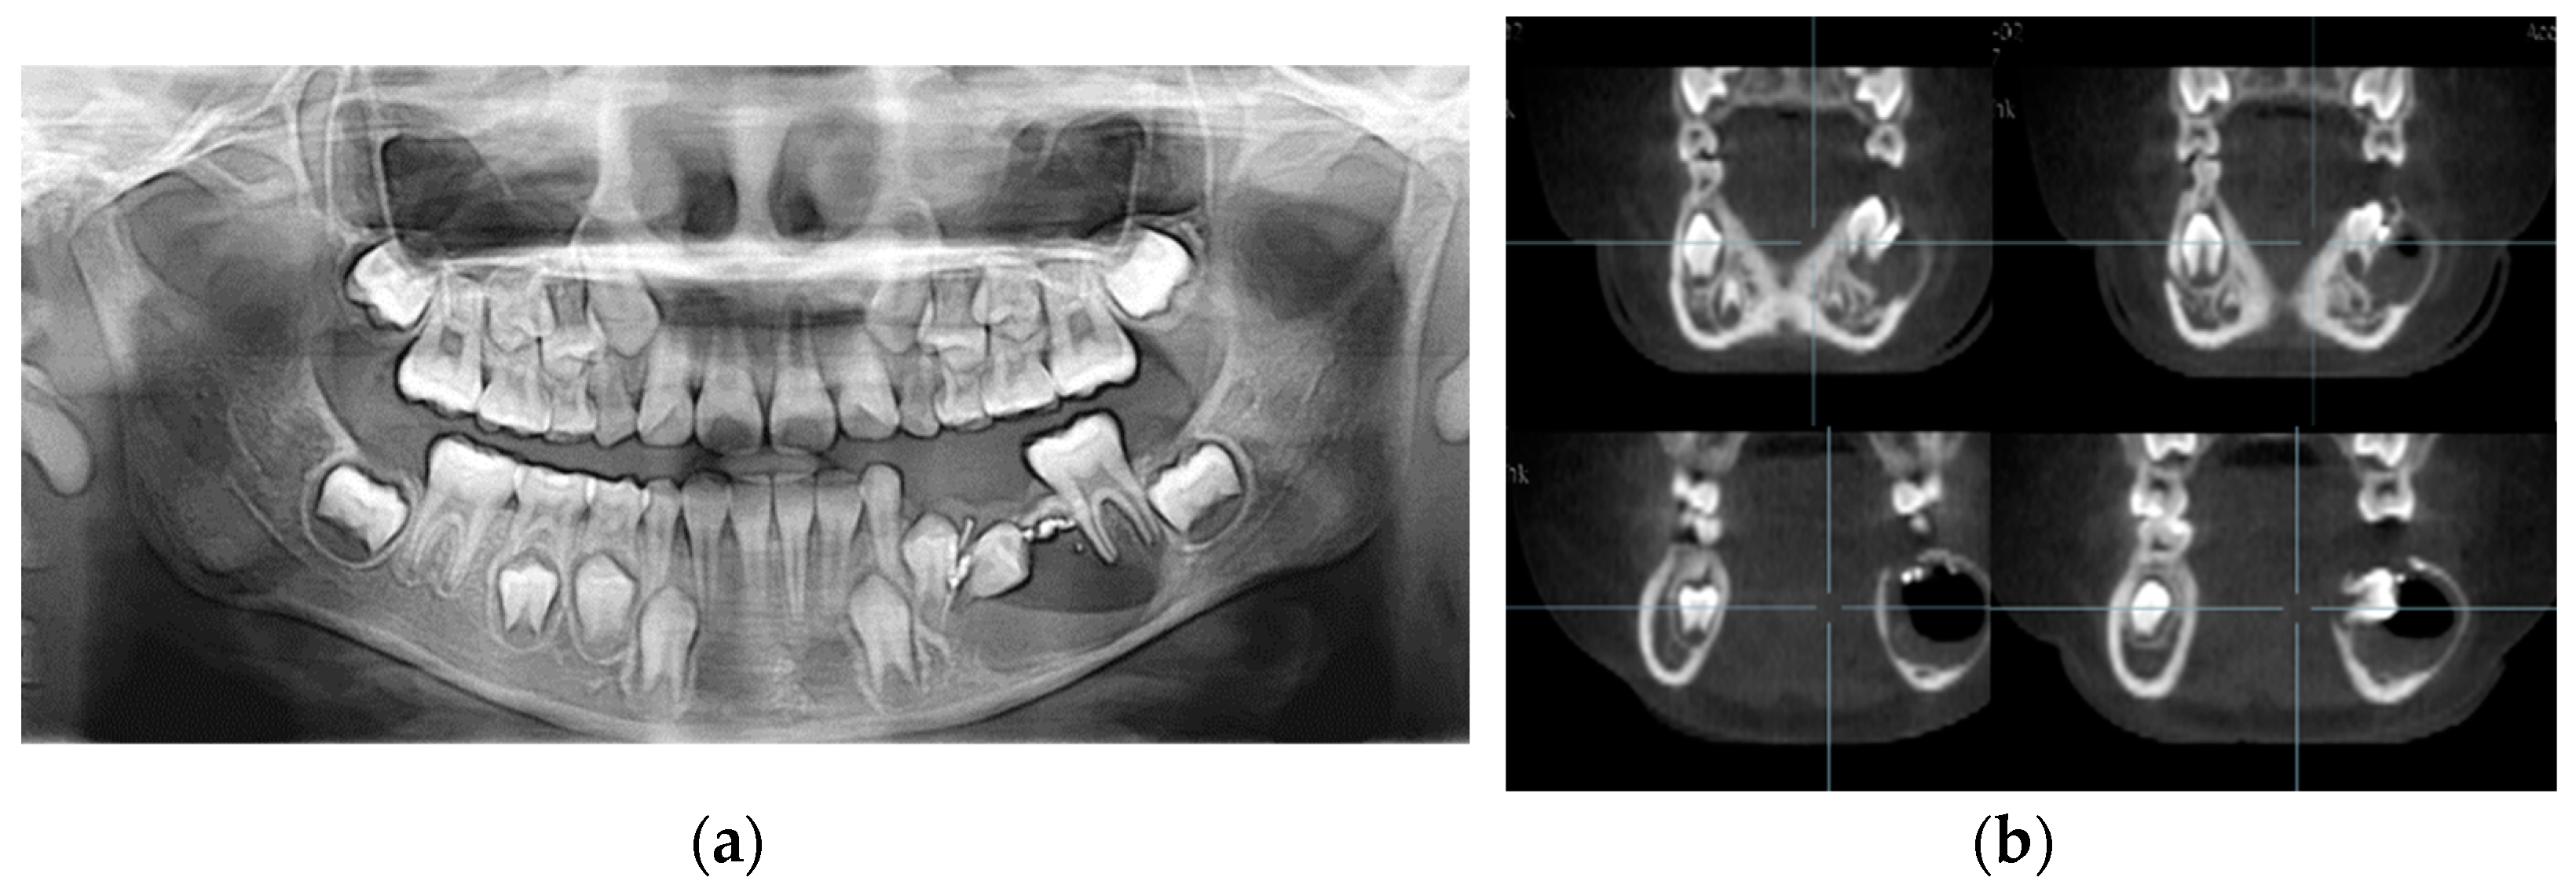

An 8-year-old boy visited the Department of Pediatric Dentistry of Kyung Hee University Dental Hospital with facial swelling on the right side of the mandible and pus discharge from the right mandibular primary first molar that had been previously treated at a local dental clinic. His medical history was unremarkable. His dental history was pulpectomy and restoration with a stainless-steel crown on the right mandibular primary first molar a year before at a local dental clinic. According to the guardian’s statement, there had been minor, painless swelling in the particular region with fluid discharge after the treatment. On dental examination, pus discharge via the right mandibular primary first molar’s disto-lingual sulcus was shown. He had poor oral hygiene and facial swelling on the right side of the mandible. Radiological examination showed a cystic lesion in the successive right mandibular first premolar region with buccal bone expansion and root resorption of the affected primary molar. In addition, a broken file was identified at the distal root tip of the affected primary molar (Figure 7).

Figure 7.

Initial visit: (a) panoramic radiograph; (b) cone-beam computed tomography; the cystic lesion around the successive right mandibular first premolar can be seen and the buccal bone swelling are observed; (c) periapical radiograph. A broken file is noted on the distal root tip of the affected primary molar (red arrow).

Under local anesthesia, the right mandibular primary first molar was extracted, marsupialization of the cyst associated with the successive permanent tooth was performed at the second visit, and the separated file was retrieved simultaneously. A removable space maintainer (RSM) with a tube was placed to facilitate the irrigation of the cystic lesion, and the patient’s caregiver was instructed to perform saline irrigation twice daily (Figure 8). Postoperatively, analgesics and antibiotics were prescribed for 3 days, and a 0.13% chlorhexidine mouth rinse was prescribed.

Figure 8.

The extraction of the right mandibular primary first molar and cyst marsupialization were performed: (a) intraoral photo after treatment; (b,c) removable space maintainer (RSM) with a tube; (d) intraoral photo with RSM.

Three days post-treatment, the patient had no complaints, and facial swelling had reduced. Three weeks post-treatment, the facial swelling had nearly subsided, and the RSM was eliminated. Two months post-treatment, the cystic lesion had reduced in size, and the occlusal surface of the mandibular right first premolar was visible intraorally (Figure 9).

Figure 9.

Two months after the marsupialization: (a) intraoral photo; (b) panoramic radiograph.

Four months post-treatment, the bone expansion was remarkably reduced, and dens evaginatus was identified on the premolar. The patient showed no clinical symptoms.